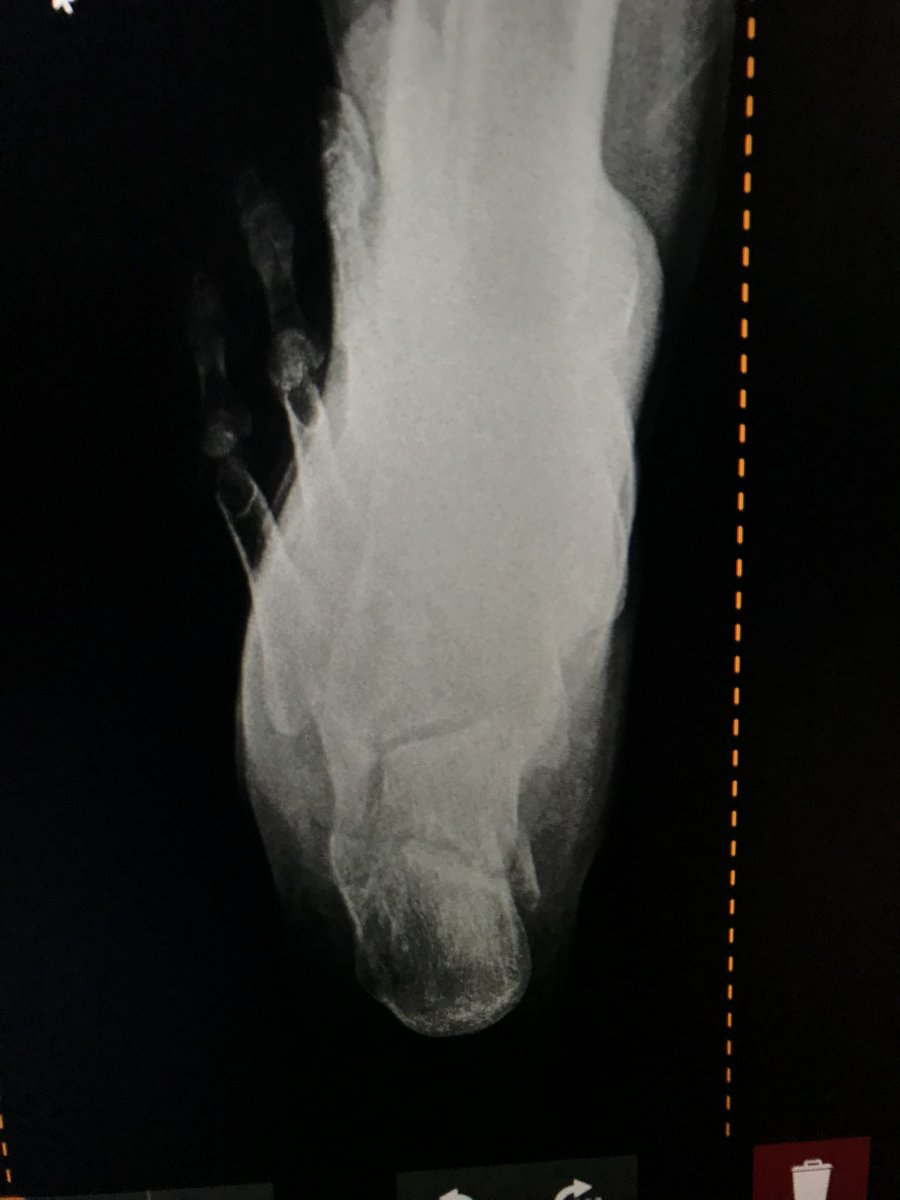

تشرفت في اخر عامين برئاسة قسم جراحة العظام في مستشفى الملك فهد بالمدينة، وكرّست عملي لـ جراحات الركبة المعقدة والإصابات الرياضية والمناظير ..